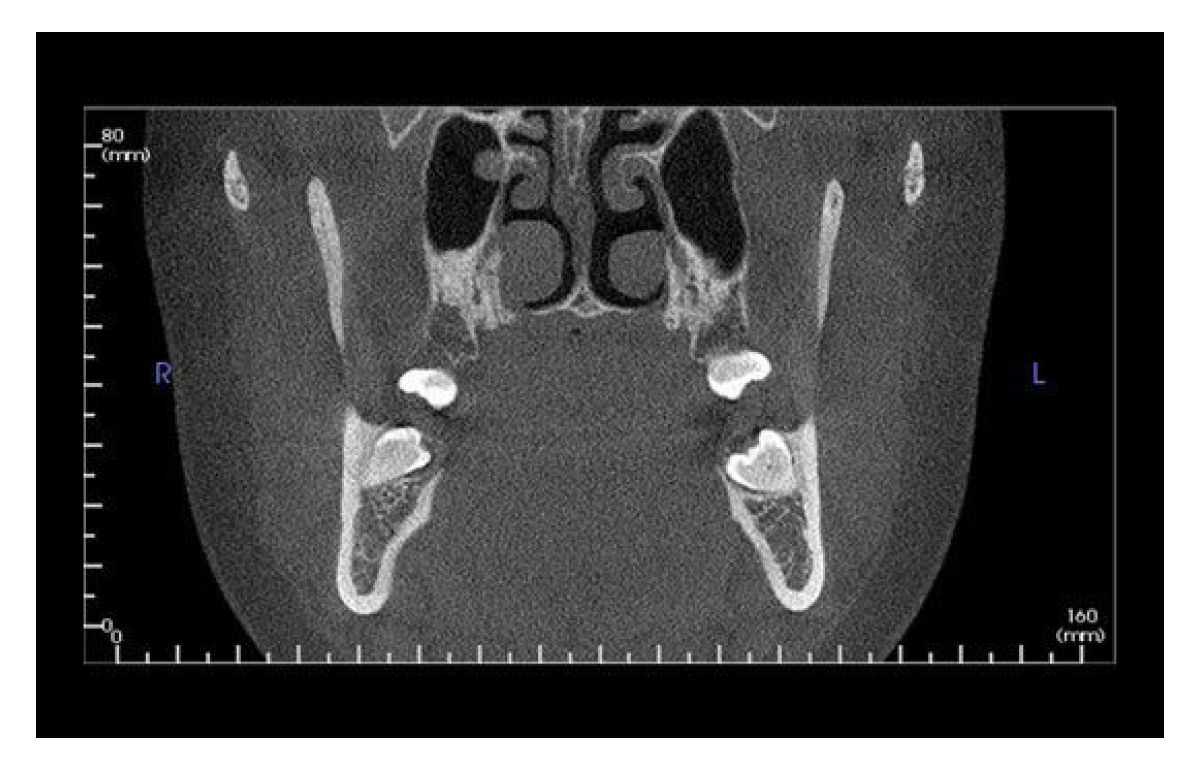

Designed to accommodate the widest range of clinical applications, the V17 is the most flexible of the V-Series options. This unit has a maximum and scalable FOV of up to 23 cm x 17 cm. The V17 is used most often by orthodontists, oral maxillofacial surgeons and oral radiologists.